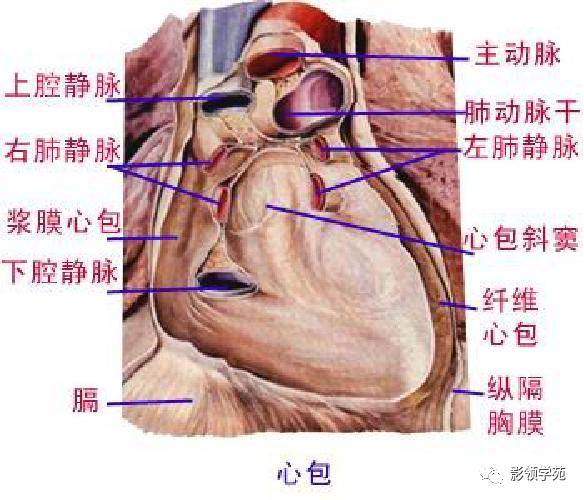

心血管系统

心血管系统